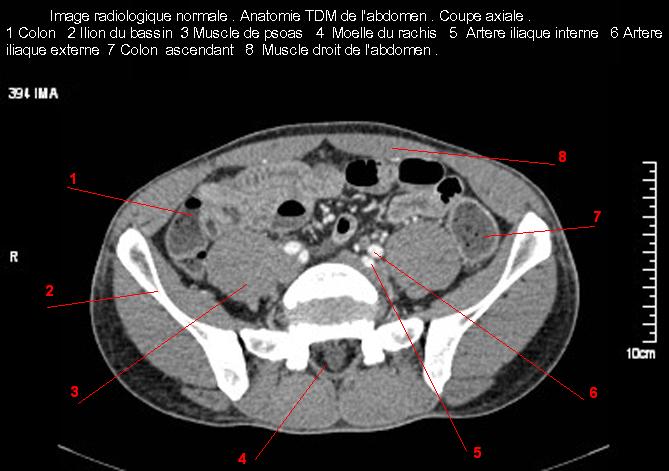

Images radiologique TDM normale de l'abdomen et tube digestif en coupe axiale ( CT scanner )  :

Coupe axiale     Coupe frontale      Coupe  sagitale